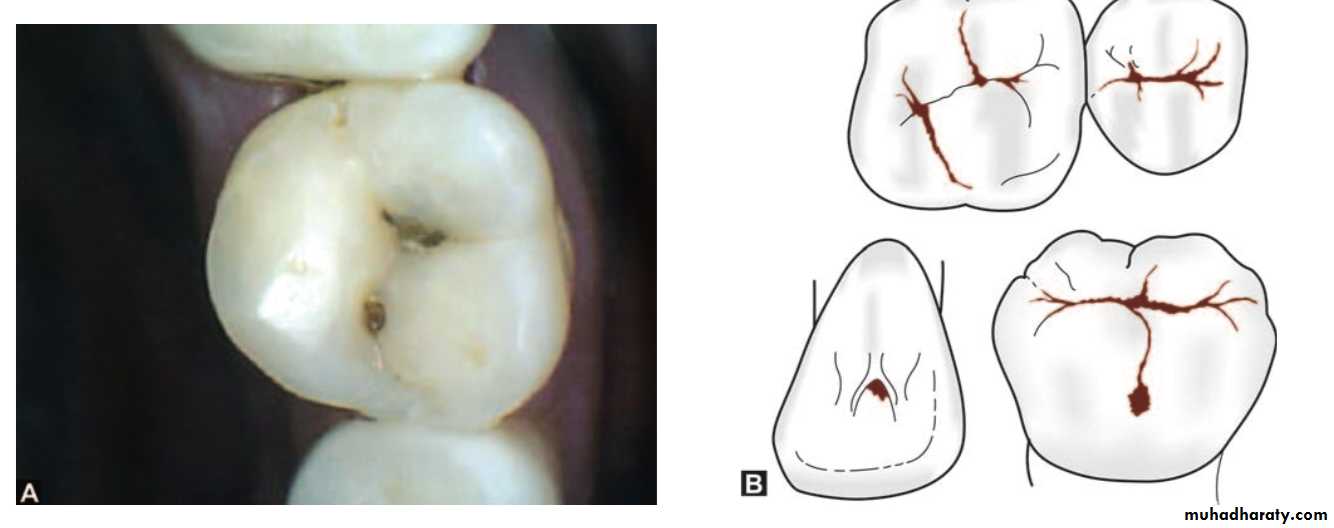

Preparations on the proximal surface of anterior teeth and not involving the incisal angles are class IIIClass IV

Preparations on the proximal surface of anterior teeth also involving the incisal angle come under class IVClass V